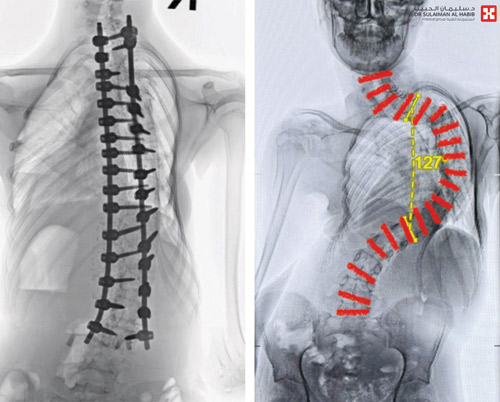

بفضل من الله تمكن مستشفى الدكتور سليمان الحبيب بالقصيم من إنهاء معاناة طفلة عمرها «13» سنة، من انحراف حاد ومتطور بعمودها الفقري «الجَنَف»، بلغت زاويته «127» درجة، وذلك عبر عملية كبيرة ومعقدة استمرت «8» ساعات متصلة، ذكر ذلك د. هاني الجهني استشاري جراحة المخ والأعصاب والعمود الفقري، رئيس الفريق الطبي المعالج. وقال إن المريضة راجعت المستشفى وهي تشتكي من عدة أعراض حادة ومتطورة، كعدم القدرة على التنفس والحركة بشكل طبيعي، مع ضعف في الأطراف وتشوه كبير وتعقيدات صحية أخرى.

وقد أجريت لها سلسة من الفحوصات الدقيقة أظهرت نتائجها وجود انحراف حاد بالعمود الفقري بلغت زاويته «127» درجة. وقد درس الفريق الطبي الحالة ووضع خطة علاجية عاجلة للحيلولة دون إصابتها بالمزيد من المضاعفات.

ووفقا للخطة العلاجية أجرى الفريق عملية للمريضة تم فيها تقويم العمود الفقري، وتثبيت ودمج الفقرات، واستمرت العملية التي استغرقت 8 ساعات بسلاسة، واستخدمت فيها مجموعة من أحدث الأجهزة التي ساهمت مع الكوادر الطبية عالية الكفاءة والتأهيل بالمستشفى ولله الحمد في إنجاحها. وبعد العملية نقلت المريضة وهي بحالة مستقرة إلى العناية المركزة وبقيت بها «4» أيام، ومن ثم نقلت إلى غرفة التنويم وتحسنت حالتها بسرعة ثم غادرت المستشفى وهي بصحة جيدة.

وأضاف د. الجهني أن المريضة استعادت لاحقاً المظهر الطبيعي، ووضع الجلوس واستقامة الظهر، كما استعادت قدرتها على الاستلقاء والنوم على ظهرها، بعد تعديل وضعية الحوض والكتف، وتخلصت من كافة الأعراض التي كانت تعاني منها قبل العملية، كما أن طولها زاد عدة سنتميترات، وعادت لممارسة حياتها بصورة طبيعية.